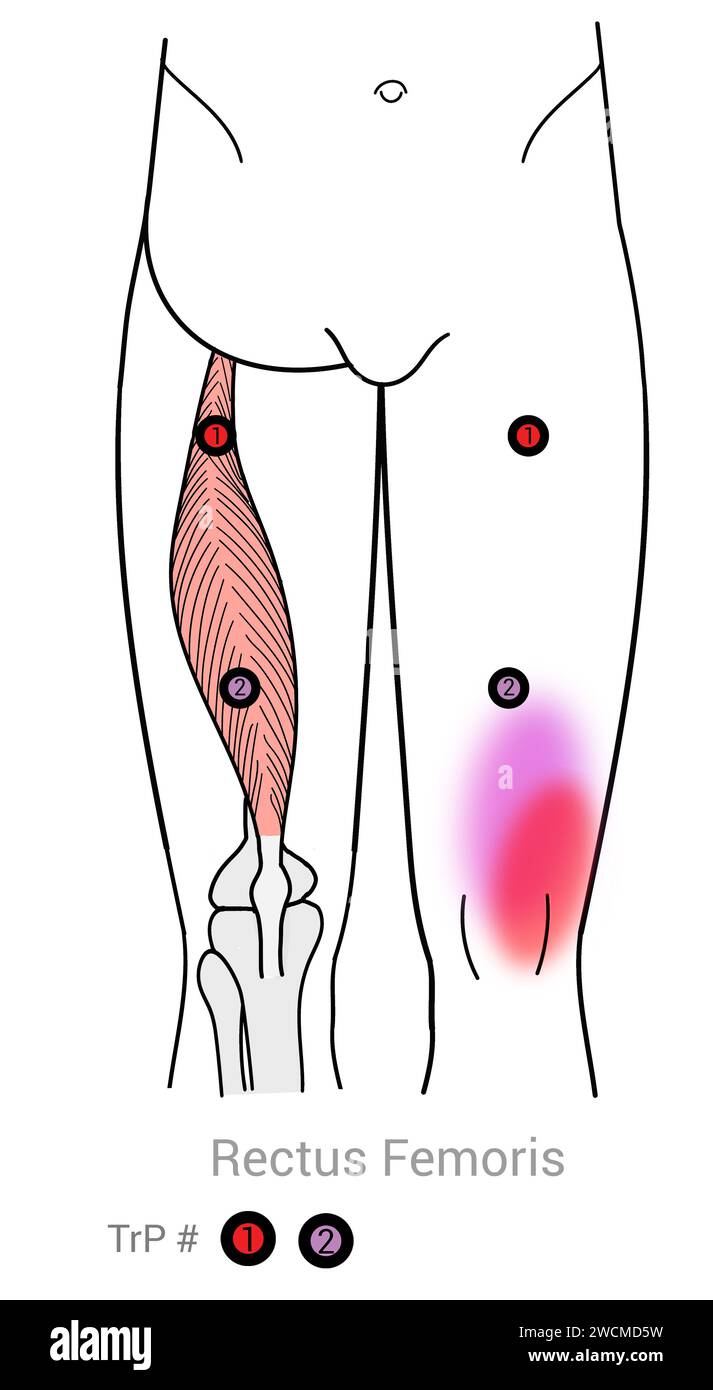

Rectus fémoris : points déclencheurs myofasciaux et localisations douloureuses associées Banque D'Imageshttps://www.alamyimages.fr/image-license-details/?v=1https://www.alamyimages.fr/rectus-femoris-points-declencheurs-myofasciaux-et-localisations-douloureuses-associees-image592977781.html

Rectus fémoris : points déclencheurs myofasciaux et localisations douloureuses associées Banque D'Imageshttps://www.alamyimages.fr/image-license-details/?v=1https://www.alamyimages.fr/rectus-femoris-points-declencheurs-myofasciaux-et-localisations-douloureuses-associees-image592977781.htmlRF2WCMD5W–Rectus fémoris : points déclencheurs myofasciaux et localisations douloureuses associées